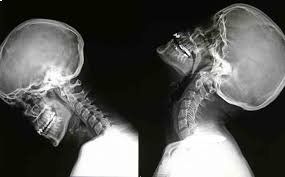

La radiologia convenzionale è l’esame di primo livello per lo studio di molteplici distretti corporei e in particolare dell'apparato respiratorio e scheletrico (cranio, colonna vertebrale, segmenti ossei). Questa metodologia fornisce importanti indicazioni di base su molte patologie, sia traumatiche che degenerative e artrosiche nonché malformative. La radiologia convenzionale si risulta anche di grande efficacia per individuare patologie o problematiche all'apparato urinario e all'addome, da approfondire successivamente con esami diagnostici più accurati e precisi.